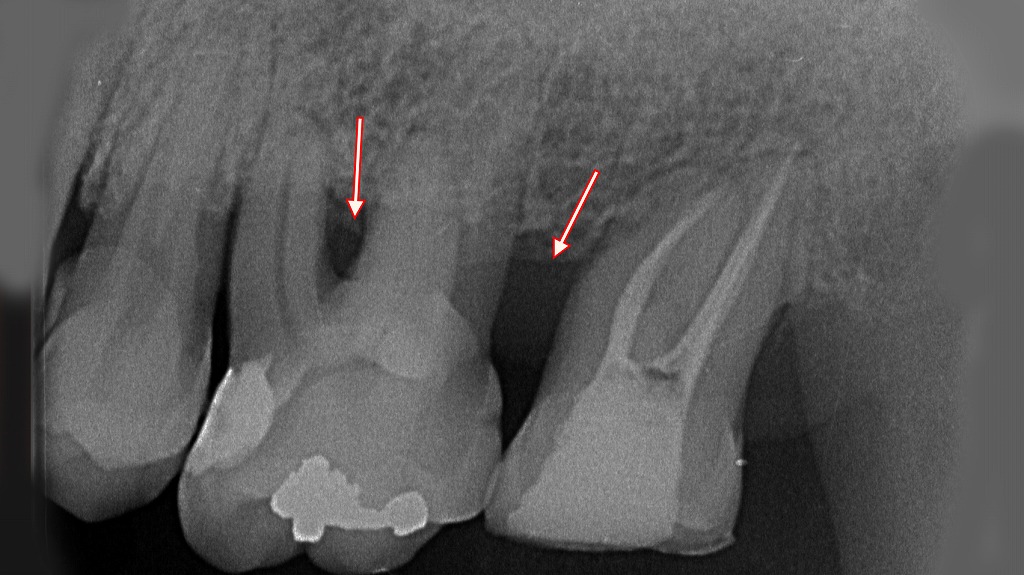

中度の歯周病が進行したサイン:歯ぐきの炎症と骨の吸収が見られる症例

矢印で示された部分の歯ぐきには強い炎症がみられ、赤く腫れた状態です。歯ぐきの縁が下がり、歯肉退縮が進んでいる部位も確認できます。また、このような炎症はプラーク・歯石の付着と深い歯周ポケットによって起こります。

同部位のX線写真を確認すると、**歯を支える歯槽骨が大きく吸収しており、中程度の歯周病(中等度歯周炎)**に該当する所見です。特に前歯部では歯根の大部分が露出し、歯の動揺が起きやすい状態です。